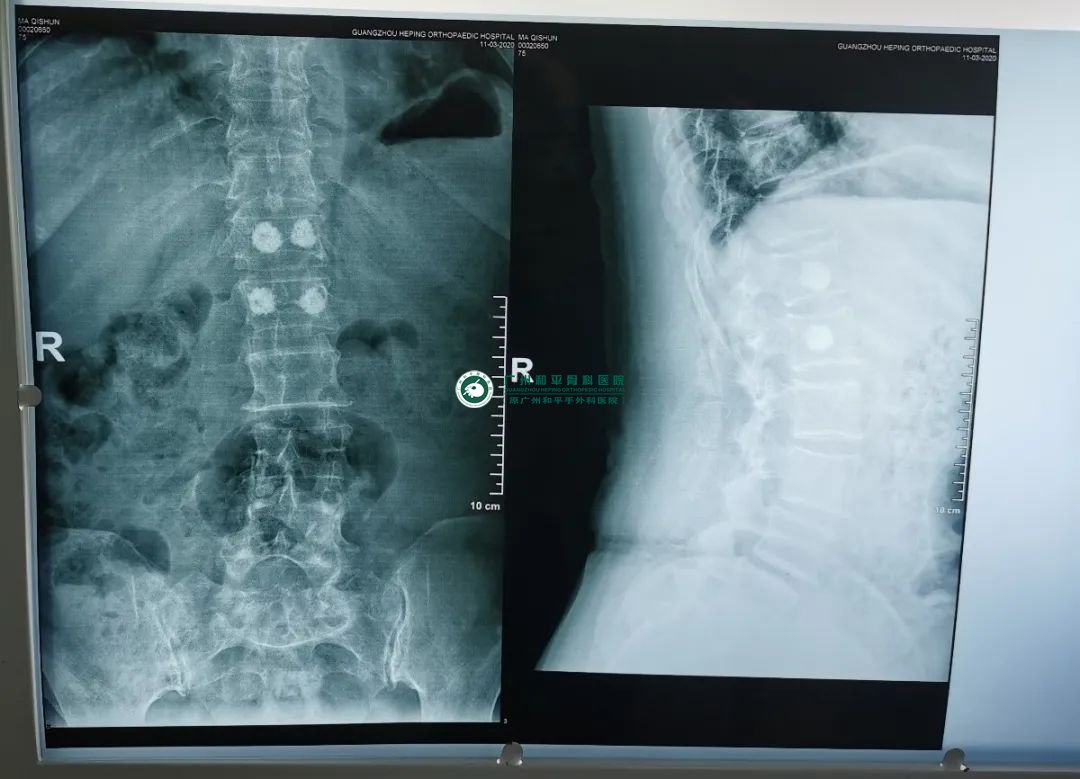

3月10日上午8:30,李奶奶被推进手术室,创伤显微手外科一区医生团队为她进行手术,术前李奶奶还对医生们说辛苦了,医生团队让李奶奶放心会尽全力帮助她减少病痛的。术中医生团队在患者椎体前1/3注入骨水泥,手术进行很顺利。

术后一周李奶奶恢复良好